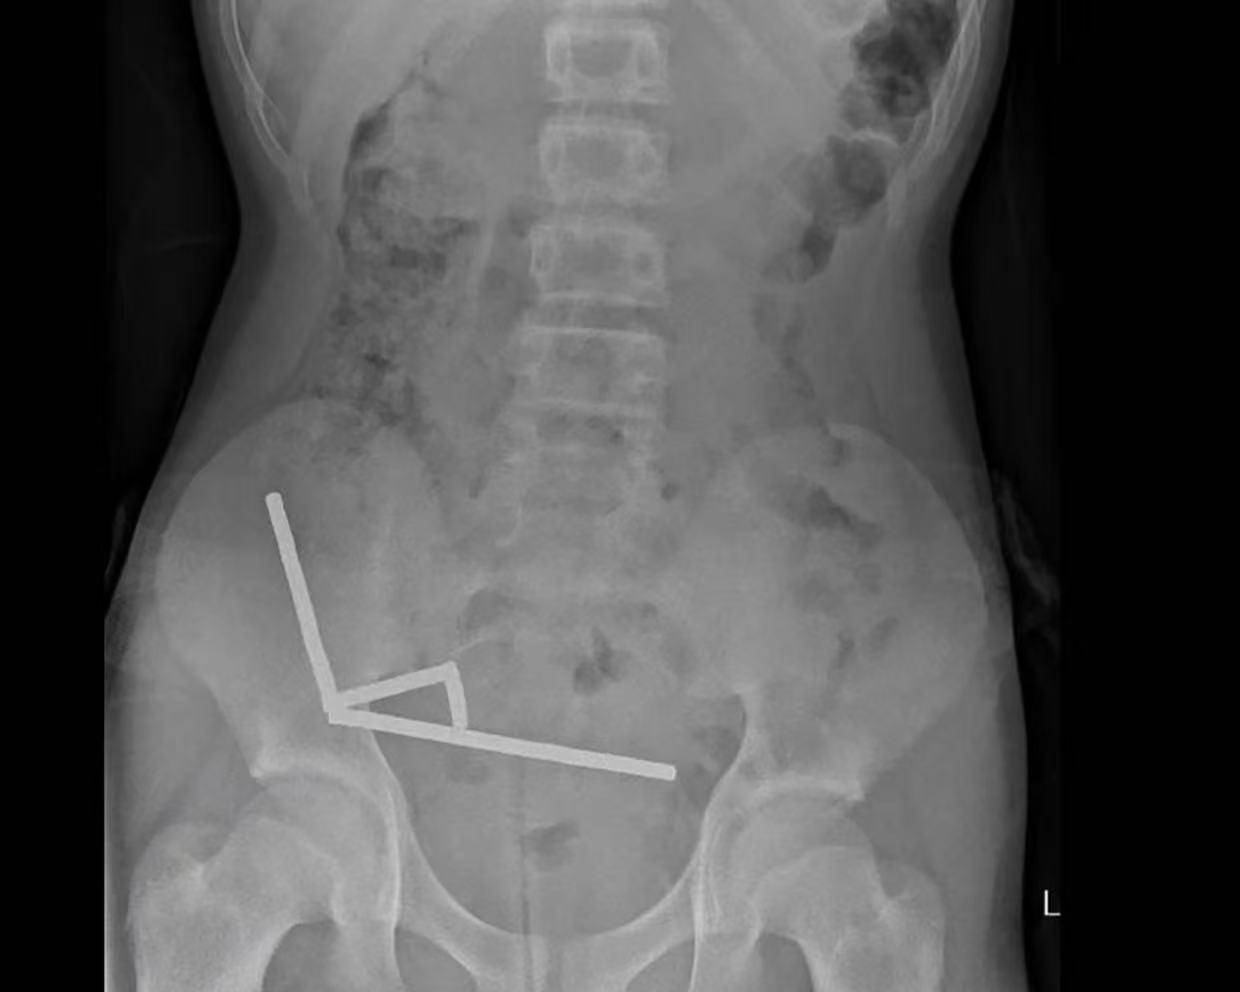

近日,新西兰一名13岁男孩吞下多达100颗在网上购买的大功率磁铁,接受了手术将其取出。医生表示,手术中不得不切除其部分肠组织。 据悉,这名未透露姓名的少年在持续...